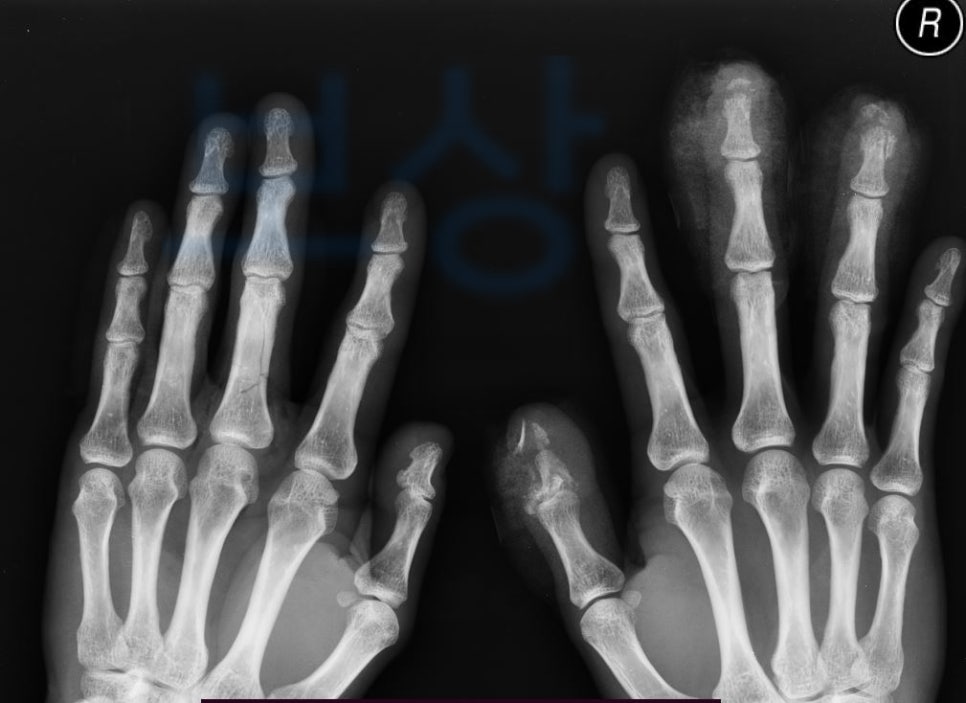

김@@님의 보상 사례 함께 보시며 내 사고와 비교해 보세요. 회사에서 일하시다 낙하물이 손에 떨어져 산업재해 사고를 당하셨습니다.

김@@님은 응급실 내원하여 정밀 검사를 받으셨고 손가락골절수술 시행하게 되었죠.

양손에 낙하물이 떨어져 압궤 손상 진단을 닿았고 양손 다 골절 및 힘줄 손상에 혈관도 손상되었습니다. 진단코드는 s678 및 s6253, s6262, s6264, s6558, s6688 김@@님은 손가락골절수술 후 재활치료를 받고 계셨는데요,